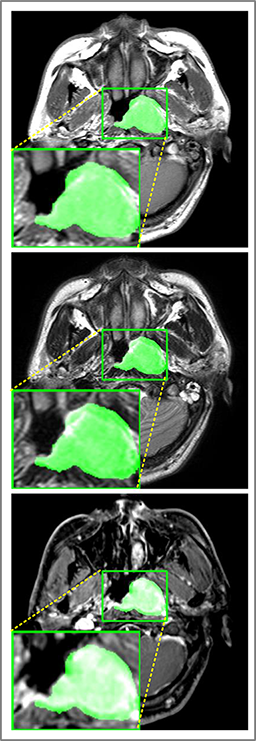

Comparison with ground truth. Some predicted results of MMFNet are shown in 2D images and 3D images in Figure 7 and Figure 8. As shown in these figures, although the shape and size of NPC are varied from each other, MMFNet can still accurately determine the regions of NPC and obtain the accurate contours of tumors. Through analyzing 2D images in figure 7, MMFNet has a capacity to fuse multi-modality MRI to reduce the confusion brought by intensity’ similarity between nearby tissues and NPC. The values of , and of MMFNet are shown in Table 1. MMFNet can reach the best results with , and .

Comparison with related works. Table 1 reports the values of , and for different methods. Predicted masks of different methods are illustrated in Figure 9 and Figure 10, which respectively present results in 2D and 3D images. Through comprehensively analyzing these results, the proposed MMFNet actually have the following properties: